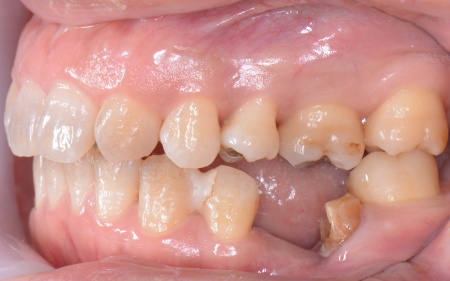

50代女性 インプラント・矯正・被せ物治療で見た目と噛み合わせを改善した症例

「以前治療した左下奥歯が思うように噛めない。また、矯正治療を受けた前歯でうまく噛めない」とご相談いただきました。

拝見したところ、左下奥歯(第1大臼歯)は以前、歯根分割処置が行われていました。

しかし残していた歯根の状態も悪化しており、治療しても温存は困難と判断しました。

さらに患者様は全体的に歯並びや噛み合わせに問題があり、特に上下の前歯は噛んだ際に隙間ができ食べ物を噛み切りにくい状態です。

過去に矯正治療を受けていても、治療が不十分であったり治療後に歯並びが後戻りしたりすることで歯並びが乱れる場合があります。